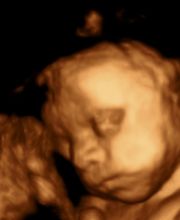

OstetriciaGalleria